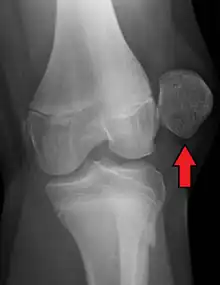

| X-ray showing a patellar dislocation, with the patella out to the side. | |